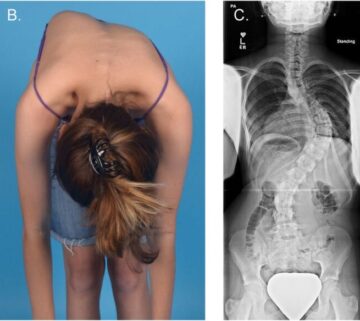

هل يؤثر اعوجاج العمود الفقري على العمر؟ كم يمكن للشخص أن يعيش مع الاعوجاج؟ يشعر الكثير من الأهالي والمرضى بالقلق عندما يسمعون أن طفلهم أو أحد أفراد أسرتهم يعاني من اعوجاج العمود الفقري (Scoliosis).

هل يؤثر اعوجاج العمود الفقري على العمر؟ | الإجابة الكاملة للأهل والمرضى يُعد اعوجاج العمود الفقري (الجنف) من أكثر مشكلات العظام شيوعًا عند الأطفال والمراهقين وحتى البالغين. وعندما يسمع المريض أو الأهل هذا التشخيص